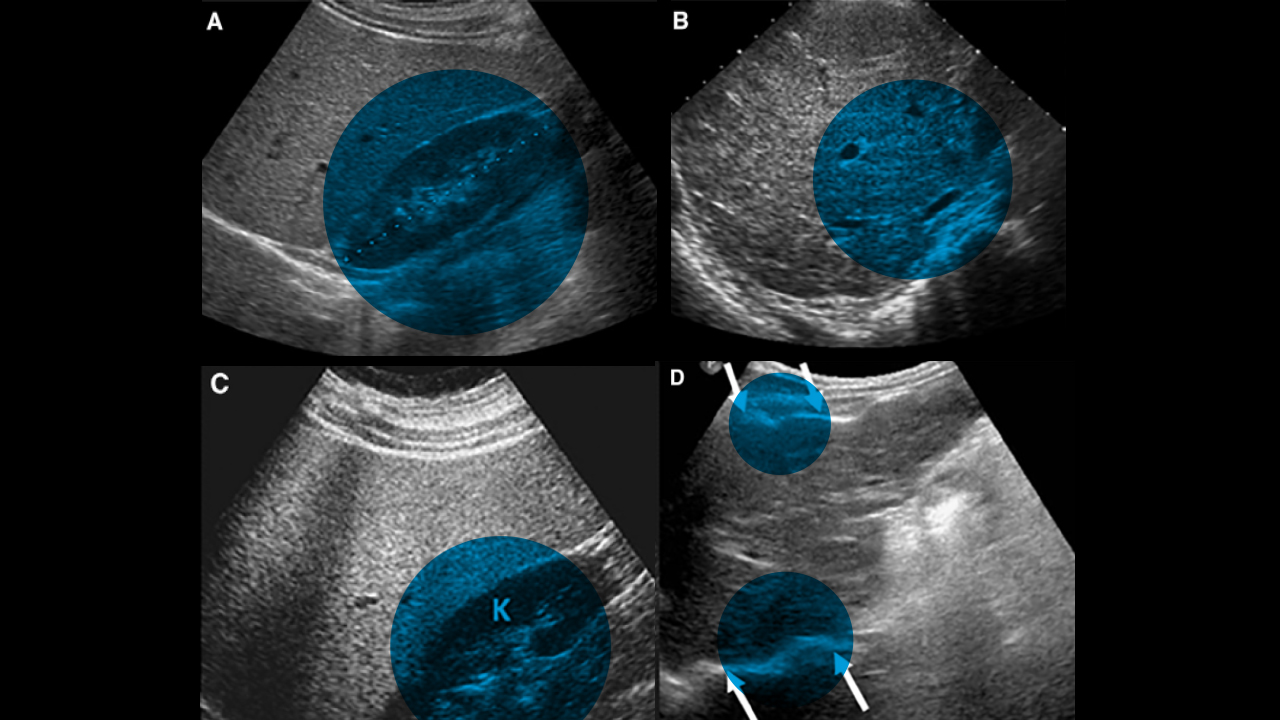

One early breakthrough of the CFLD-NET proved that ultrasound technology provided an affordable, effective way to determine when a CF patient had at least a 50% risk of developing advanced liver disease. Dr. Narkewicz and his team built upon that success by collaborating with radiologists to develop standardized order sets for these ultrasounds, which ensure a consistent, comprehensive approach to how the scans are conducted and evaluated.

These standardized ultrasounds are also used in a calculation created by the CFLD-NET, which has been adopted by providers around the world to signal potential liver involvement before a patient’s cystic fibrosis progresses. “We developed this prognostic algorithm where you can plug in age, ultrasound finding and a blood test called the GGT-to-platelet ratio that will identify any individual’s risk,” Dr. Narkewicz says. “Then, we collaborate closely to review all patients who are identified as at risk of having liver disease in that space.”